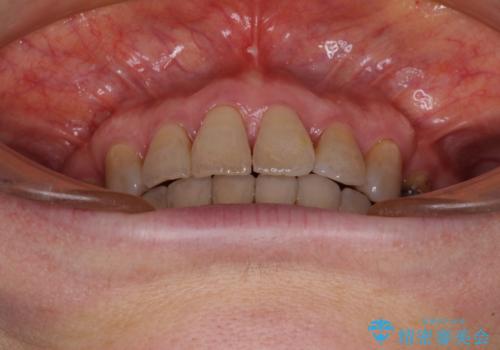

- 突出した口元を引っ込めることを希望して来院された患者様です。

上下左右第一小臼歯4本を抜歯して、口元を改善するワイヤー矯正を行うこととしました。

長年気にされていた口元の突出感が改善されたため、もっと若い時分に矯正をすればよかったと思われていました。